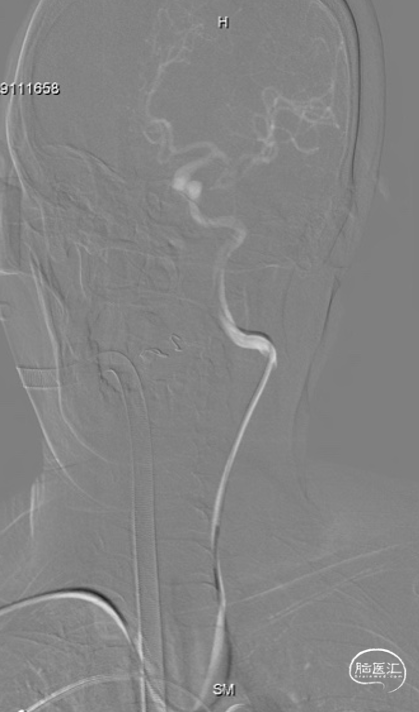

右侧桡动脉穿刺,穿刺成功后置入6F薄壁动脉鞘,随后使用TRUST技术置入Tethys®中间导引导管(内衬5F Simmon导管)输送至锁骨下动脉,弓上勾选至左侧颈总动脉后,Tethys®中间导引导管顺滑输送至左侧颈内动脉成功建立治疗通路,为后续致密栓塞及释放支架提供重要支撑.

建立治疗通路后,在微导丝引导下分别将塑性好的弹簧圈微导管及支架微导管超选至左侧颈内动脉床突旁动脉瘤及左侧大脑中动脉远端;释放支架后,填入弹簧圈实现动脉瘤的致密填塞;在整个过程中Tethys®中间导引导管提供稳定支撑。